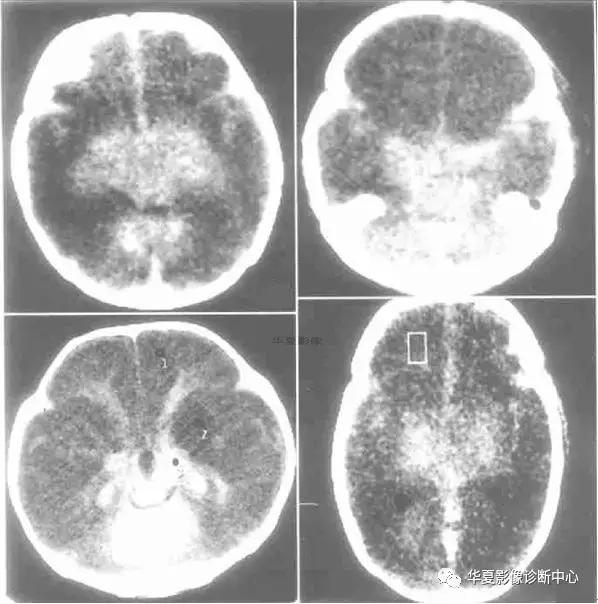

七、反转征:

儿童弥漫性脑白质和灰质的密度减低、伴有灰白质界限不清或消失,或灰白质密度反转,而丘脑、脑干和小脑密度相对增高根据“反转征”出现时间分急性和慢性2期。急性指当时CT扫描即有“反转征”,慢性为弥漫性脑萎缩/脑软化伴“反转征”。急性期神经病理学改变主要为大脑皮质和白质发生急性神经元坏死和脑水肿,脑干及丘脑淤点状出血。Baenziter等认为缺氧缺血后大脑皮层第Ⅲ、Ⅳ层神经细胞最易受损,缺血后12小时以上大脑皮层神经细胞即发生嗜酸样变性,基质发生凝固性坏死,2~3 天轴索开始变性,7天左右出现成胶质细胞、脂肪颗粒和新生血管,2~4周形成空洞和软化,进一步论述了缺氧缺血后皮层神经细胞的病理过程。基底节和丘脑损害所发生的密度增高目前有几种认识:国内学者认为系缺氧后上述区域发生大理石样变性所致,表现为神经元的丧失、星形细胞胶样变性及髓鞘过度形成,尤其壳核背外侧与丘脑腹外侧髓鞘化最活跃,需氧量最高,代谢旺盛,对缺氧缺血敏感,因此受累也最为严重。有的则认为是严重缺血后1~2周新生毛细血管网的大量增加或与大脑的白质深部髓质静脉扩张淤血有关,甚至有人认为不是密度增高,而是正常脑组织密度。这种密度增高是相对的,虽然在急性期脑中央区域的密度增高个体间存在一定的密度差异,但本组从未见有像脑血管破裂出血那样的高密度,CT值多在22 HU左右,因此这种密度增高是相对的。

“反转征”的分期,急性期应以生后当时CT扫描结果为准。一般来说,生后3天多以脑水肿为主,其后为脑实质缺氧缺血性损害,所以生后5~10 天扫描较为可靠。慢性期以生后3~8周为妥,此期已出现明显脑软化、脑萎缩,脑实质密度明显低于急性期。急性“反转征”的患儿需要呼吸支持和重症监护,延误治疗者可转变为慢性“反转征”,其密度变化更具有特征性。有人认为重症病人在3个月时即可发生脑软化和脑萎缩,发生率约占HIE病例的20%。与此同时,丘脑与脑干的密度增高较急性期更加显著,如同“增强”一样,CT值22~26 HU,丘脑形态轮廓勾画清楚,犹如雪山的“山丘”,出现这种明显反差的影像学表现可能与脑软化的低密度衬托有关,若不仔细的观察和测量CT值易误为脑出血。

“反转征”主要发生在重度HIE病例中,因此“反转征”可视为重度HIE少见而重要的征象,可把它作为HIE诊断及分级和评价预后的重要依据。

CT“反转征”是新生儿重度缺氧缺血性脑损伤的一种重要CT征象,但并非特异性,也可以在某些疾病中如外伤(虐待伤)、病毒性脑炎等出现。特别应注意慢性“反转征”与HIE的并发症鉴别。众所周知,HIE常见并发症为外部性脑积水和局限性脑软化灶和脑萎缩,前者不存在鉴别问题,后者CT上脑软化灶多发生在顶枕叶或双侧脑室旁白质内,多为局限性,而慢性“反转征”则表现为半球弥漫性低密度区,同时基底节及丘脑等脑中央区域密度增高明显,表现特殊,这点对鉴别诊断有相当重要的价值。因此,重度窒息儿大脑灰白质密度弥漫性减低伴灰白质界限消失或密度反转以及基底节、丘脑、脑干和小脑密度相对增高是重度HIE的特征性CT表现,是诊断急、慢性CT“反转征”的重要依据。急性期脑室受压变窄和慢性期脑室扩大主要与脑水肿和脑软化/脑萎缩有关。“反转征”一旦出现,高度提示脑组织有不可逆性脑损伤存在,预后大多不良,即使存活也将发生脑瘫或智力障碍等后遗症。